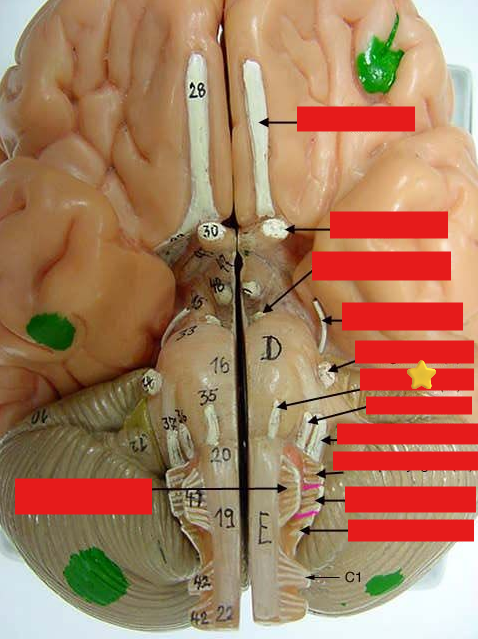

cranial nerves

12 Terms

1

olfactory

2

optic

3

oculomotor

4

trochlear

5

trigeminal

6

abucens

New cards

7

facial

8

vestibulocochlear

New cards

9

glossopharyngeal

New cards

10

vagus

New cards

11

accessory

New cards

12

hypoglossal

New cards